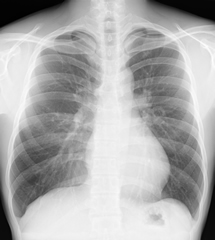

一般撮影

単純X線撮影は一般的に「レントゲン」といわれている検査です。主に胸部・腹部・骨格系の撮影を行います。全ての撮影室で最新のFPD(FPD:Flat Panel Detector)を使用しており、従来よりも被ばく線量が少なく、鮮明な画像を提供しています